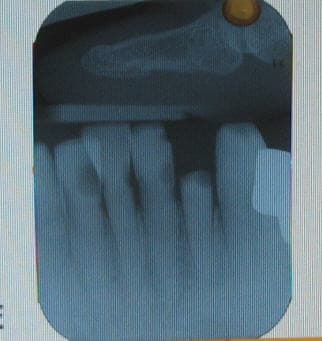

Vue du cabinet ce jour...

P1000709 tbwpfl - Eugenol

P1000708 aazhix - Eugenol

Hanna

11/09/2009 à 00h17

Il y avait un cirque?

wild

11/09/2009 à 09h49

exact, cirque de passage dans le patelin. Sympa le dépaysement sans quitter le boulot.